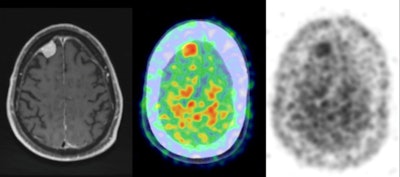

Postcontrast axial T1-weighted MRI demonstrates a right frontal meningioma (left), while the PET/CT axial color map fusion image (center) shows intense PiB activity within the meningioma. Also, an axial PET image (right) demonstrates intense PiB activity within the meningioma. Images courtesy of Dr. Derek Johnson.Amyloid connection